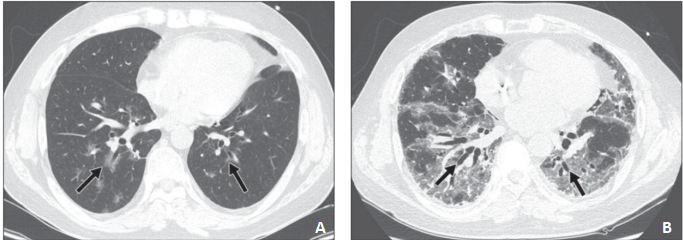

图7 24岁男性行HSCT治疗急性髓系白血病后出现呼吸困难